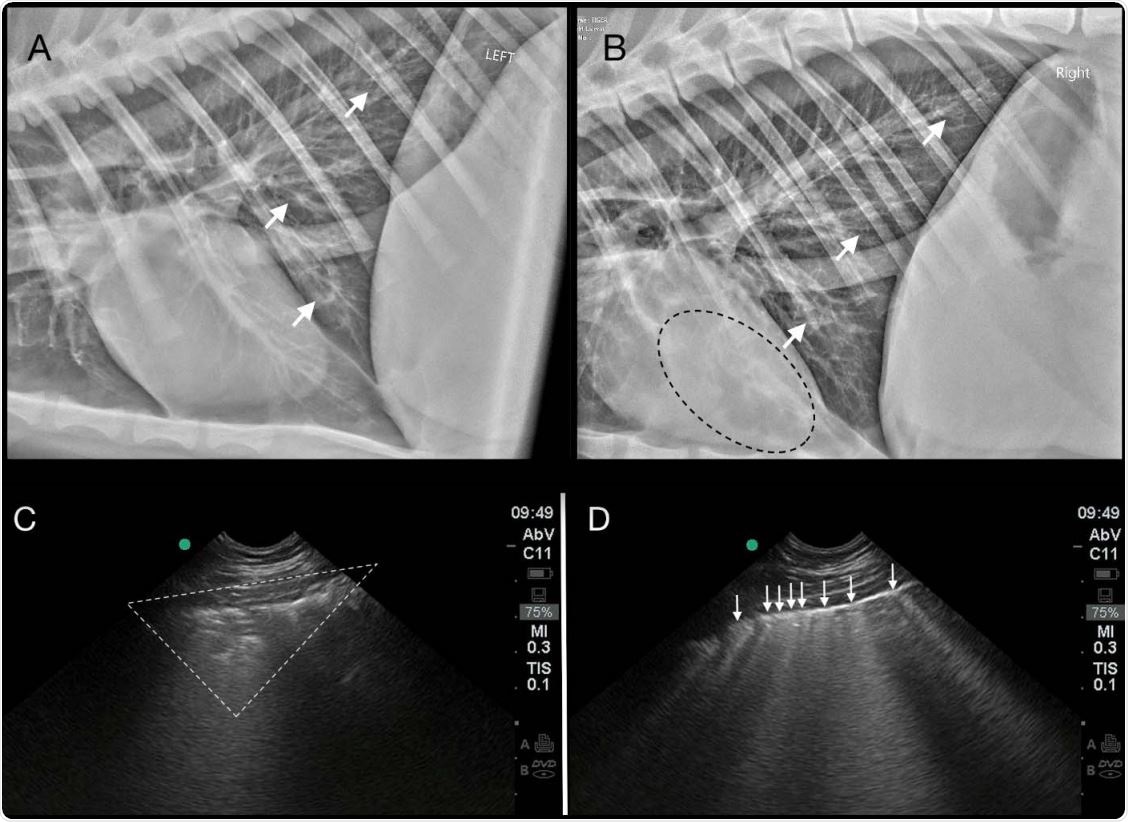

Thoracic imaging abnormalities in the index Tiger (T1) with SARS-CoV-2 infection. A generalized bronchial pattern with peribronchial cuffing and bronchiectasis (white arrows) is present in the caudal lung on left lateral (2A) and right lateral (2B) radiographs. Anesthesiaassociated atelectasis is seen as an alveolar pattern superimposed over the heart (black dotted line) (2B). Pulmonary ultrasonography reveals peripheral consolidation (white dotted triangle) (2C), and coalescence of vertical B-lines (white arrows) (2D) indicating AIS (alveolar-interstitial 580 syndrome).

This tissue damage, along with signs of respiratory disease and a “white lung” appearance, is consistent with the imaging results reported for infected humans, say Bartlett and colleagues.